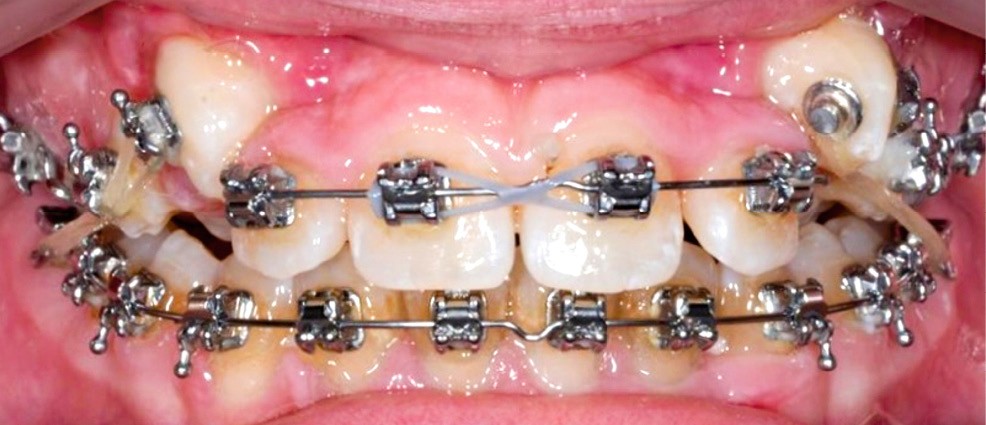

La patiente consulte à l’âge de 9 ans pour la malposition de ses incisives latérales maxillaires. Elle présente une occlusion de Classe I bilatérale sur un schéma normodivergent avec une dysharmonie dento-maxillaire en denture mixte. À l’arcade maxillaire, elle présente une endoalvéolie avec rotations mésiopalatines de 16 et 26.

Sur la radiographie panoramique, on observe une transposition des canines maxillaires en place d’incisives latérales, au contact des racines de 11 et 21.

Un appareil multi-attache est mis en place avec une prescription MBT en .022 x .028. une fois les faces vestibulaires des canines maxillaires apparentes. 13 et 23 ne sont pas prises en charge dans l’arc pour éviter les effets parasites sur les dents adjacentes. Leur traction est poursuivie avec des élastiques de Classe II (1/4” – 3.5 oz) en port nocturne. Ces élastiques sont portés sur un bouton palatin pour la 23 afin de corriger sa rotation mésio-vestibulaire. Une fois les canines suffisamment proches du plan occlusal, elles sont prises en charge dans un arc continu en suivant les séquences suivantes : .014, .018 et .019 x .025 Niti. Une fois l’arc .019 x .025 en Niti en place pendant huit semaines, l’arc transpalatin est déposé. L’arcade mandibulaire suit cette même séquence d’arcs avec l’ajout d’un arc en acier .019 x .025 avec courbe de Spee inversée pour aider à la correction de la supraclusion.